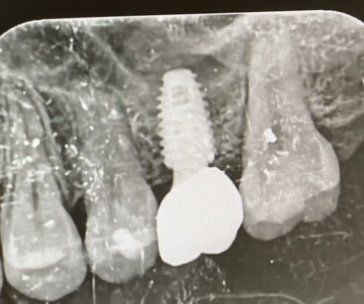

제가 부분교정 후, 임플란트를 하였는데 교정 틀을 뺀후 임플란트 앞쪽 치아가 심하게 흔들립니다. 고개를 움직일때, 입모양을 바꿀때 치아가 움직이고 빠진것같은 그쪽이 가벼운 느낌도 들어요. 담당의사분은 괜찮다고 시간이 지나면 괜찮다고 하시는데 벌써 3주째인데 그대로 예요 ㅠㅠ 얼마나 더 시간이 지나야 괜찮아질까요? 임플란트한쪽으로 먹으라고 하는데 쌩 치아 빠질까 무서워서 그쪽으로 잘 먹지도 못하고있어요(엑스선 촬영 사진 첨부)

현재 엑스레이 사진으로는 치아에 문제는 없어 보입니다. 다만 현재 임플란트 시술 이후 치아의 빡빡한 증상이 혹시 있으셨나요? 아니면 전체적인 파노라마 사진이 필요할 것으로 보입니다. 임플란트 이후에 교합이 변하여 현재 흔들리는 치아가 먼저 닿을 경우 관련 증상이 나타날 수도 있습니다. 그러나 대부분은 임플란트 이후에 없던 자리에 치아가 생김으로써 관련 부위의 이질감이 나타나는 경우가 대부분입니다. 사진상으로 보아서는 치아가 빠질 정도로 흔들리거나 이상이 있어 보이지는 않습니다. 조금 더 기다려보시고 한달이 지나도 관련 증상이 나아지지 않거나 줄어들지 않는다면 병원 방문 후 교합검사 및 다른 검사들을 시행해보시길 바랍니다.

임플란트 앞쪽치아는 사진상으로는 괜찮아보입니다.

오히려, 임플란트 치아가 사진상으로 방사선투과성이 보입니다.

물론, 방사선사진의 특성상 저렇게 나올 수 도 있기때문에, 확실히 말씀드리긴 어렵습니다.